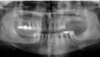

Cas 2: Vues panoramiques

AVANT REHABILITATION

PENDANT REHABILITATION 3 SECTEURS MOLAIRES

APRES REHABILITATION 3 SECTEURS MOLAIRES